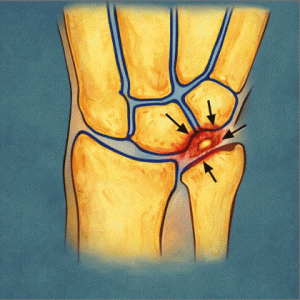

El síndrome de estrés tibial medial (MTSS, por sus siglas en inglés) es una causa habitual de dolor en la cara interna de la tibia. Afecta a deportistas, especialmente corredores de media y larga distancia, y puede limitar significativamente el rendimiento.

Se caracteriza por un dolor difuso, no puntual, que aparece al correr y puede persistir incluso en reposo si no se trata adecuadamente.

La teoría tradicional apuntaba a un desequilibrio entre el impacto repetido y la capacidad de adaptación del hueso. Sin embargo, investigaciones recientes como la de Naderi et al. (2020) indican que una actividad muscular anómala, especialmente del músculo sóleo, podría estar implicada en la aparición de esta lesión.

El estudio utilizó electromiografía de superficie (EMG) para medir la actividad del sóleo durante la fase de apoyo en carrera. Se observó que las personas con mayor activación de este músculo presentaban mayor riesgo de desarrollar MTSS.

Este hallazgo sugiere que no solo el impacto o la técnica influyen, sino también cómo trabaja la musculatura estabilizadora profunda del tobillo.

Una activación elevada y sostenida del sóleo puede generar una tracción repetida sobre el periostio tibial, facilitando la aparición del síndrome.